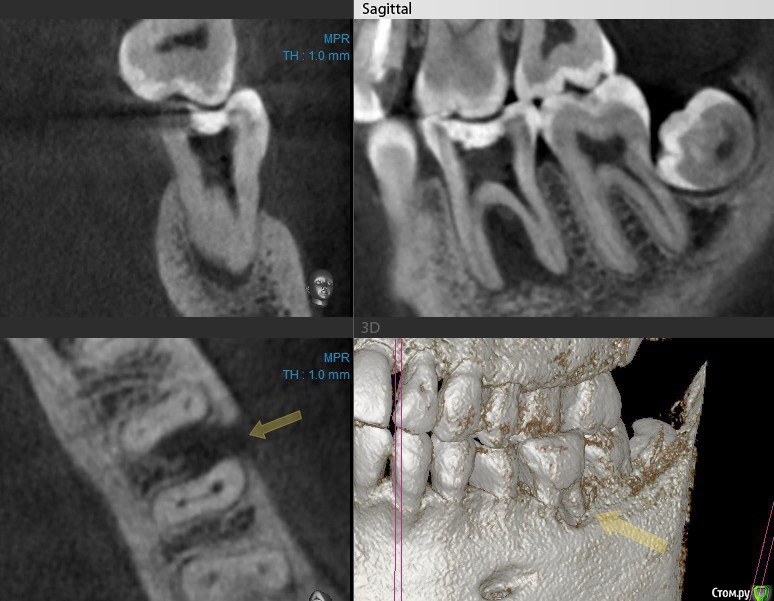

Сева северный Опубликовано 21 апреля, 2016 Поделиться Опубликовано 21 апреля, 2016 (изменено) .Хотелось бы выслушать мнение по зубу 4.6Пациент пришел по рекомендации, коллеги, из сторонней клиники. . Как бы вы поступили в данной ситуации? ( Скриншоты КТ, прилагаются) Изменено 21 апреля, 2016 пользователем Сева северный Ссылка на комментарий

Сева северный Опубликовано 21 апреля, 2016 Автор Поделиться Опубликовано 21 апреля, 2016 (изменено) Мужчина. Возраст: около 50,Жалобы. на болевые ощущения ..отсутствуют. Зуб ранее лечен, имеется старая пломба с нарушенным прилеганием, по границам- кариес. Пальпация, перкуссия безболезненна, в области бифуркации при надавливании, появляется жидкость, желтоватого цвета. При зондировании зонд погружается в межкорневое пространство примерно на 15 мм. Изменено 21 апреля, 2016 пользователем Сева северный Ссылка на комментарий

Гарриевич Опубликовано 22 апреля, 2016 Поделиться Опубликовано 22 апреля, 2016 на трещину не похоже, я бы лечил как банальные периодонтит Ссылка на комментарий